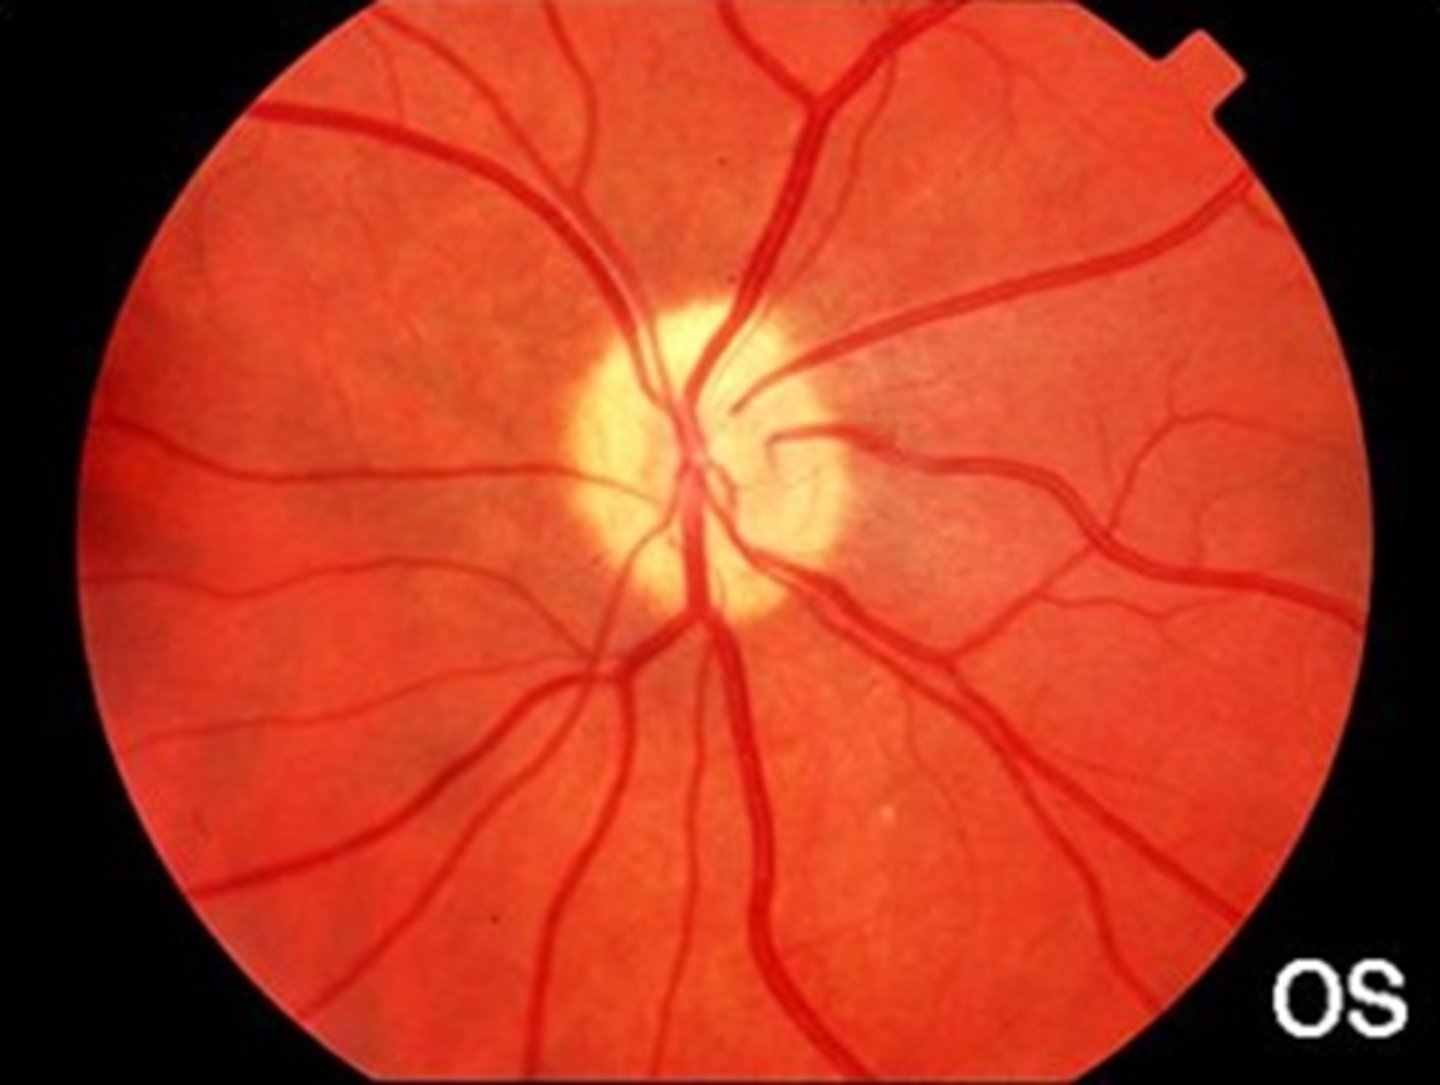

What cause of ascending optic atrophy is shown here?

AAION